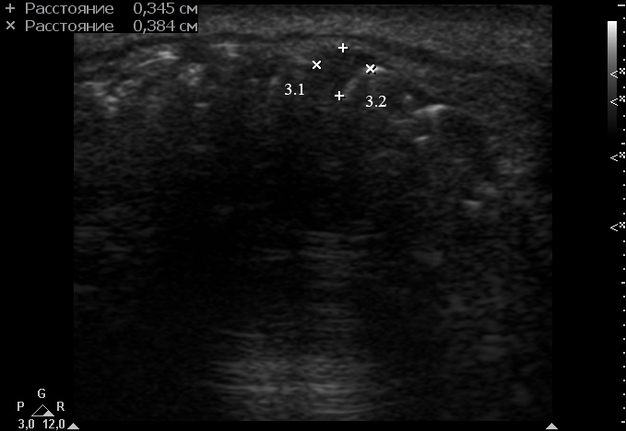

Clinical examination revealed the presence of a neoplasm on the lingual side of the alveolar process of the mandible that had grown vestibularly between the left central and lateral incisors (Fig 1). The neoplasm was mushroom-shaped, pale pink in color, elastic upon palpation, and had a pedicle. The mucosa adjacent to the neoplasm is unchanged in color and structure. The neoplasm measured 1.8 x 1.1 x 1.2 cm at the lingual aspect of the lower teeth and 0.34 x 0.38 cm at the vestibular aspect.

Anterior part of the neoplasm at the vestibular aspect of the lower teeth measured 0.34 x 0.38 cm (Fig 3). Upon the gray-scale USG the anterior part portion of the neoplasm vizualized as homogenous hypoechoic lesion with no signs of calcifications. Color Doppler USG showed no vascularity within the vestibular portion of the neoplasm (Fig 4).